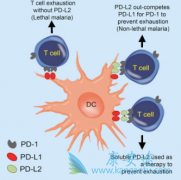

近几年,癌症治疗发生了天翻地覆的变化。以 PD-1抑制剂 为代表的癌症免疫疗法,正在逐渐成为癌症治疗的新希望。PD-1抑制剂在多个癌症治疗的临床实验中,都展现除了超过传统癌症疗法如化疗的疗效,是目前癌症治疗的领先治疗方案。 截止到目前,PD-1抗 ...